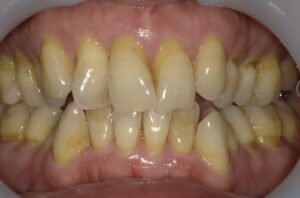

【症例2】50代・矯正は難しいと言われ半ば諦めていたガタガタの改善

「数カ所の歯科医院で相談をしたが、矯正が難しいと言われ諦めかけていた」という50代女性のケースです。前歯が元々欠損しているため真ん中を合わせることはできませんが、ガタガタはIPRや側方拡大を行い治すことができました。

仕上げに前歯のすり減りをダイレクトボンディングで直し、より整った印象にしています。

- 治療方法: ワイヤー矯正上下

- 治療期間: 12ヶ月

- 治療費用: 77万円(税込)

- 治療のリスク・デメリット:ブラックトライアングル

- ポイント: 比較的短期間のプランで、前歯の見た目と清掃性を大幅に向上させました。